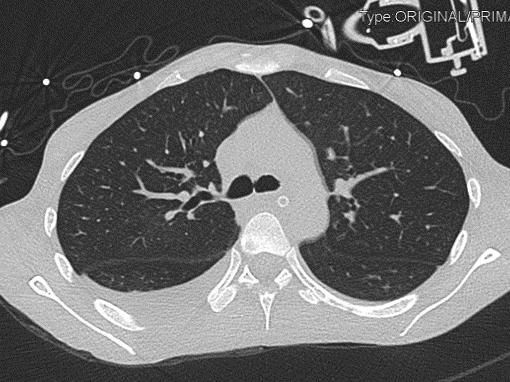

2021-4-29 CTPA:肺动脉干、左右肺动脉及其分支未见狭窄及明显充盈缺损。右肺、左肺下叶见斑片影、磨玻璃影及实变影。

胸部CT:

右肺感染吸收,双侧胸腔积液吸收,双肺散在小结节,多系炎症,左膈抬高。

患者青年女性,慢性病程;主要表现为腹胀、呼吸困难,术后出现意识障碍、II型呼吸衰竭。经呼吸机辅助呼吸、对症支持等治疗后,患者意识恢复但呼吸困难无明显改善;既往有有粉尘接触史。查体见患者极度消瘦、营养不良,双肺呼吸音粗,可闻及散在湿啰音。血气示II型呼吸衰竭、高碳酸血症,轻度贫血,低蛋白血症,电解质紊乱,炎症指标、肌酶、BNP升高,院外腹水检查示漏出液,未见肿瘤细胞;胸部CT:双肺斑片影,抗感染治疗后病灶吸收;腹部增强CT:双侧附件区分别混杂密度团块影,内见多发囊泡影;心脏彩超:右心稍大,重度肺动脉高压。